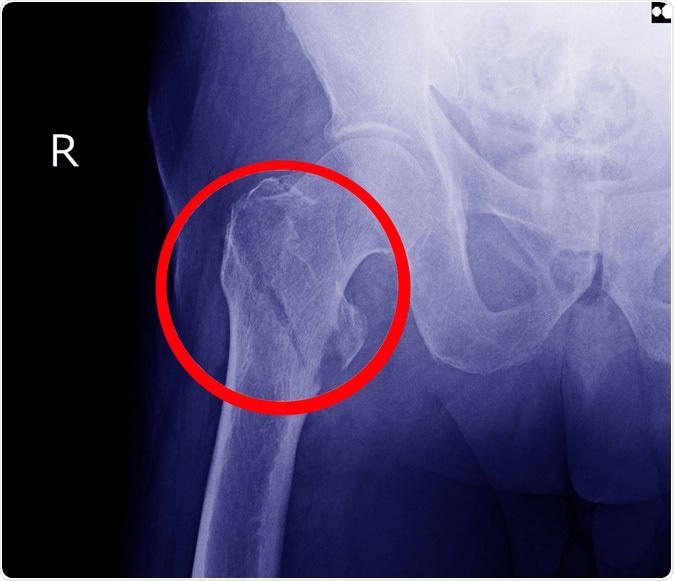

Hip fracture X-ray. Image Credit: Richman Photo / Shutterstock